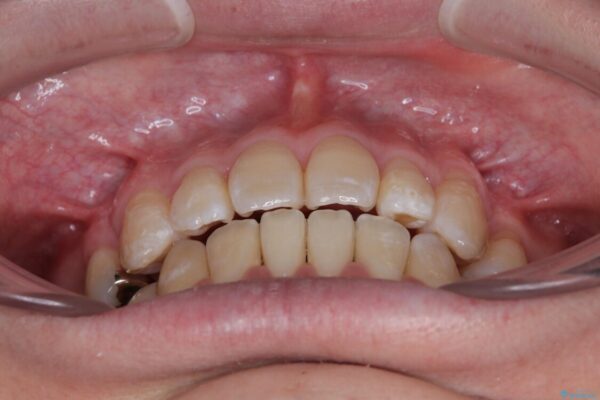

治療後

• 口元の突出感を改善!目立ちにくいワイヤー矯正で自信を持てる自然な横顔に 治療後画像